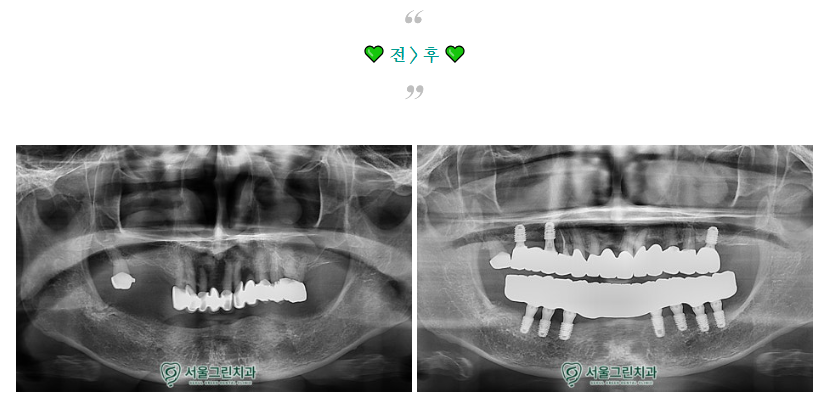

소개해드릴 분은

70대 후반 환자분으로,

아래 틀니의 헐거움과

위쪽 브릿지의 흔들림을 주소로 내원하셨습니다.

.

아래 틀니가 헐거워

음식 섭취 시 불편함을 느끼고 계셨으며,

위쪽 기존 브릿지는 흔들림으로 인해

불안정한 상태였습니다.

엑스레이 사진을 촬영하여

더욱 정밀한 체크를 진행하였고,

환자분과의 충분한 상담을 통해

치료계획을 수립해보았습니다.

위아래 모든 치료가 마무리 된 후,

구강 내 모습입니다!

치료 후 환자분께서는

틀니를 빼고 끼는 번거로움이 사라져

매우 편해졌으며,

이전보다 훨씬 안정적으로 씹을 수 있게 되었다고

만족해하셨답니다.